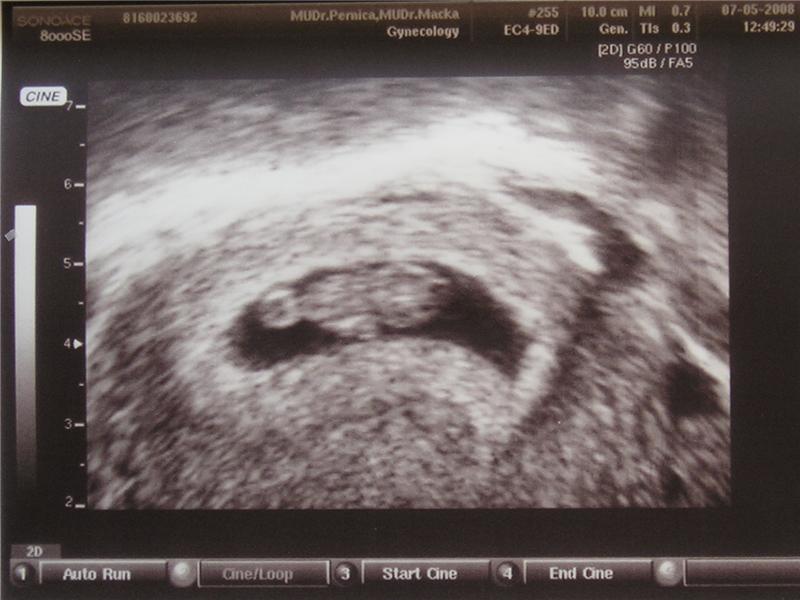

Ultrazvuk